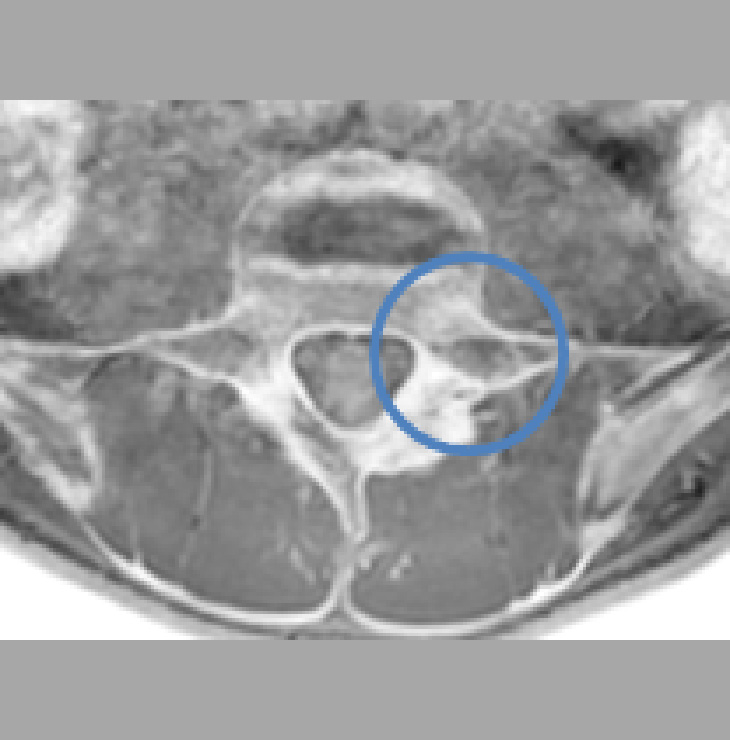

腰部脊柱管狭窄症とは

加齢、労働、あるいは背骨の病気による影響で椎間板や靭帯の膨らみ、背骨や椎間関節から突出した骨などにより神経が通っている骨のトンネルが狭くなる(狭窄)ことを言います。

検査と診断の流れ

・問診、診察ののち、X線・MRI・エコーで評価を行います。

・必要に応じて間欠性跛行テストやミエログラフィーを行います。